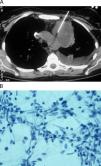

ResultadosSe estudiaron 131 pacientes con lesiones mediastínicas, 71 varones (54,2%) y 60 mujeres (45,8%) con una media de edad de 53±19 años (intervalo: 8–84 años). Un 54,5% de los pacientes era menor de 60 años. Las lesiones se localizaban en cualquiera de los 3 compartimentos del mediastino, 88 (67,2%) en mediastino anterior, 15 (11,4%) en mediastino medio y 22 (16,8%) en mediastino posterior (figs. 1 y 2). En 6 pacientes (4,6%) la lesión se extendía a más de un compartimento: en 5 casos se localizaba en mediastino anterior y medio, mientras que en otro llegaba también al mediastino posterior. En el 10% de los casos, el tamaño de la lesión era menor o igual a 2cm.